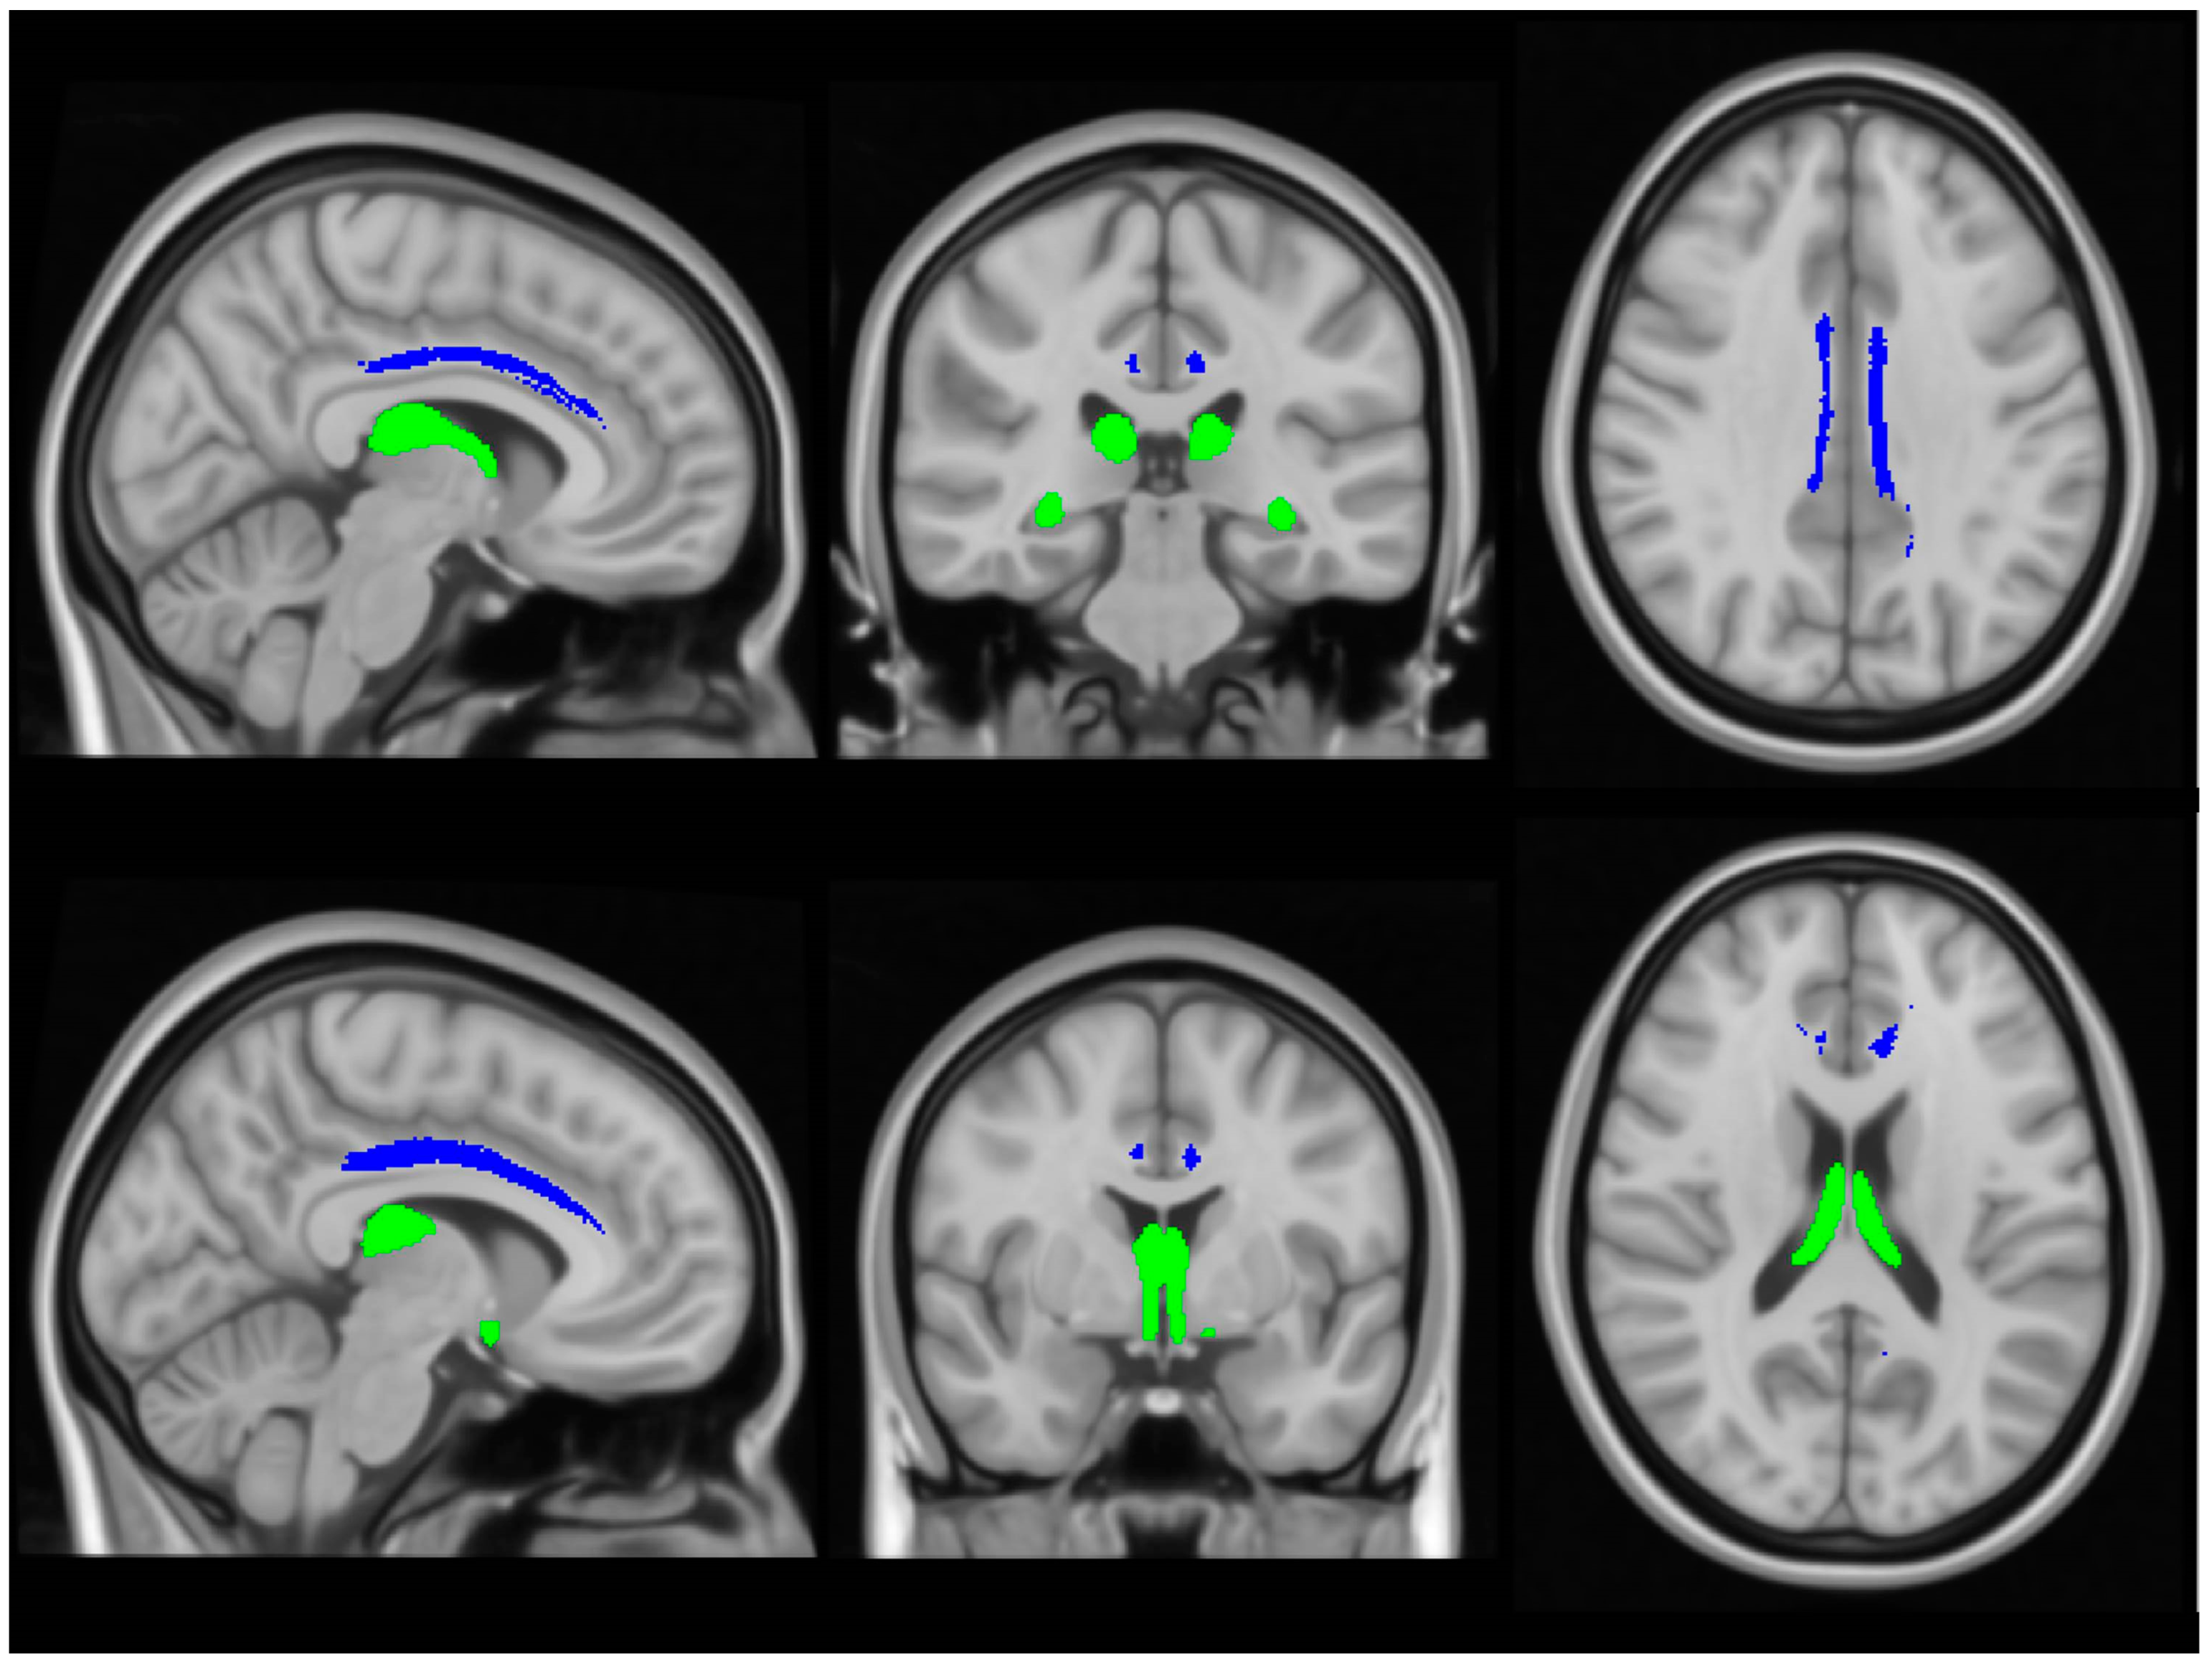

Physiologically, the limbic system and the Papez circuit (Figure 1) mediate a number of crucial functions such as motivation, emotional regulation, information registration and spatial memory, etc. [31], therefore the dysfunction of these networks in ALS has important practical ramifications. While clinical trials continue to focus solely on motor function, mobility, bulbar function, respiratory measures and composite functional rating scale scores as their main monitoring and outcome measures, the practical impact of cognitive and behavioural impairment should not be underestimated [32,33]. Neuropsychological deficits in ALS are thought to have survival ramifications, impact on caregiver burden, affect compliance with assistive devices, end-of-life decisions, adherence to therapy and participation in clinical trials [34,35].

Figure 1. The main grey and white matter components of limbic networks; the blue colour indicates the main structures of the Papez circuit.